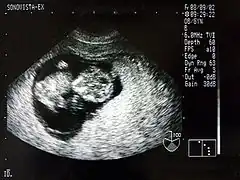

Échographie gynécologique et obstétricale

Dans le cadre de la surveillance médicale de la grossesse, une échographie permet d'obtenir une image monochrome d'un fœtus à l'intérieur du ventre de sa mère. Bien que ce soit l'utilisation la plus connue de l'échographie, on utilise également cette technologie pour la détection des troubles d'organes internes (calculs, kystes, cancers).